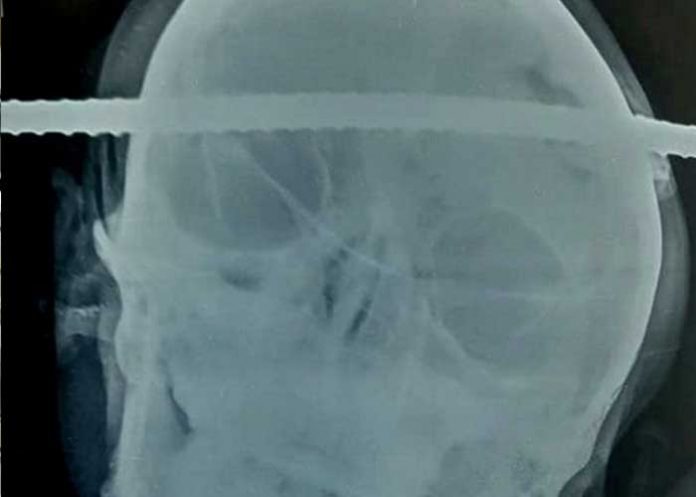

En la India, un joven se ha salvado milagrosamente luego que una barra de hierro le atravesara el cráneo, y fuera sometido a una cirugía de alto riesgo para extraerle la varilla.

Una de las varrillas se incrustó por la región temporal derecha y salió por la región frontal izquierda del cráneo. Además, la barra perforó una de sus manos.

Bahe fue trasladado en ambulancia a un hospital del vecino estado de Maharastra, y durante todo el viaje permaneció consciente. La cirugía a la que fue sometido duró 90 minutos y una vez finalizada no se presentaron complicaciones.

El neurocirujano Pramod Giri explicó que la barra dañó el tejido cerebral, lo que puede provocar en el futuro problemas como convulsiones y cambios de comportamiento, pero no representan un peligro mortal. Asimismo, indicó que el objeto oxidado pasó a tan solo unos milímetros de los principales vasos sanguíneos, que en caso de afectarlos podría haberle causado la muerte.